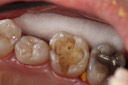

Photos of Clinical Operations

Drs. Peter Kearney, Terry McKay, John St. Germain, and Laurie Vanzella - Mentors